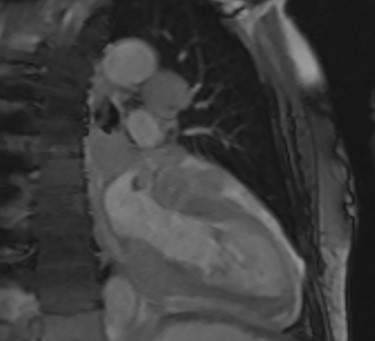

Intraoperatively, he developed new t-wave inversion on lead II of the 3-lead electrocardiogram (ECG). This resolved post-operatively, and he denied chest pain. He was kept in overnight for observation. The next morning, during the round, he reported central crushing chest pain the previous day that he had not disclosed. His ECG was repeated and demonstrated the t-wave inversion in lead II—indicating dynamic ECG changes. A troponin I level measured 27. As such, management for a non-ST elevation myocardial infarction was initiated and a cardiology consult organized, who advised continued acute coronary syndrome (ACS) treatment and an echocardiogram. This demonstrated a ‘pericardial mass (subcostal 3 cm × 2.5 cm) encroaching and extending outwards on both sides of the right atrioventricular groove’. ACS protocol was stopped and a cardiac magnetic resonance imaging (MRI) was organized (Figs 2 and 3).

This demonstrated a bulky mediastinal tissue (measuring 50% of the heart) that encased all the aorta and pulmonary artery as well as the coronary artery. It has malignant behaviour with multiple foci that breached fascial planes. It restricted the long axis of the heart but was not causing haemodynamic occlusion. It was non-resectable.

Cardiac MRI (sagittal plane) showing the lesion encasing the aorta, pulmonary artery and all coronary arteries of the heart.